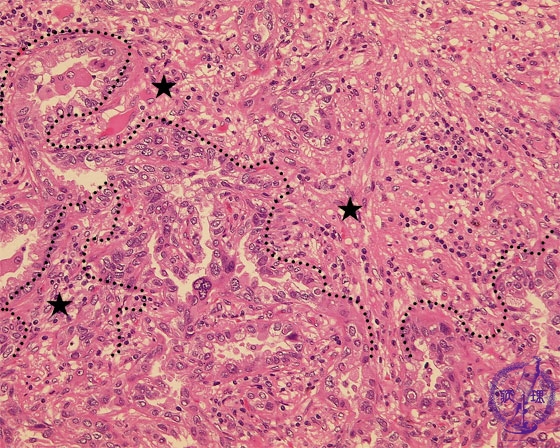

非小細胞肺癌(腺癌)ミクロ像(HE強拡大)

ミクロ像(HE強拡大):腫瘍中心部、浸潤癌の部分では腫瘍細胞は不規則な腺腔を形成しながら浸潤性に増殖している。複雑に入り組んだ間質(星印)にはリンパ球を中心とした炎症細胞の浸潤が見られる。